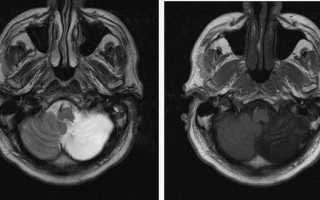

МРТ: головные боли после получения травмы. Постишемические кистозно-атрофические изменения: ишемический инфаркт левого полушария мозжечка в стадии поздней организации